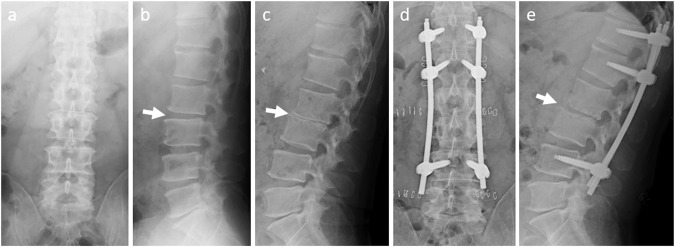

Fig. 1. Pre- and postoperative radiographs.

Antero-posterior (a) and lateral (b) radiographs taken at first presentation show that the L2–L3 disc had not collapsed (arrow). Lateral radiograph taken 25 days after admission (c) shows that the L2–L3 disc had obviously collapsed. Post-operative antero-posterior (d) and lateral (e) radiographs show that the L2–L3 disc had widened after percutaneous pedicle screw fixation (arrow).